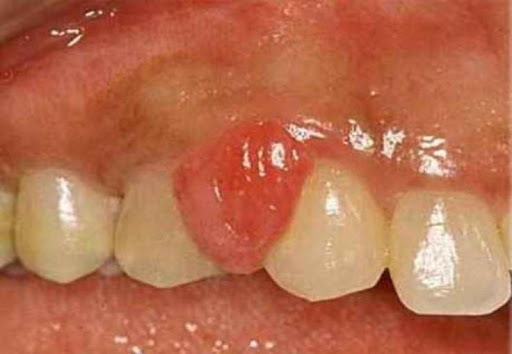

Epulis

syn. fokal fibröse Hyperplasie

- > halbkugeliges oder pilzförmiges Gebilde, das meist dem Zahnfleischrand aufsitzt. Synonym ist die Fokale fibröse Hyperplasie. Es handelt sich um eine Granulationsgewebebildung unterschiedlicher Zellstruktur